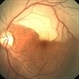

- Calcified embolus in a patient with cardiac valve disease.